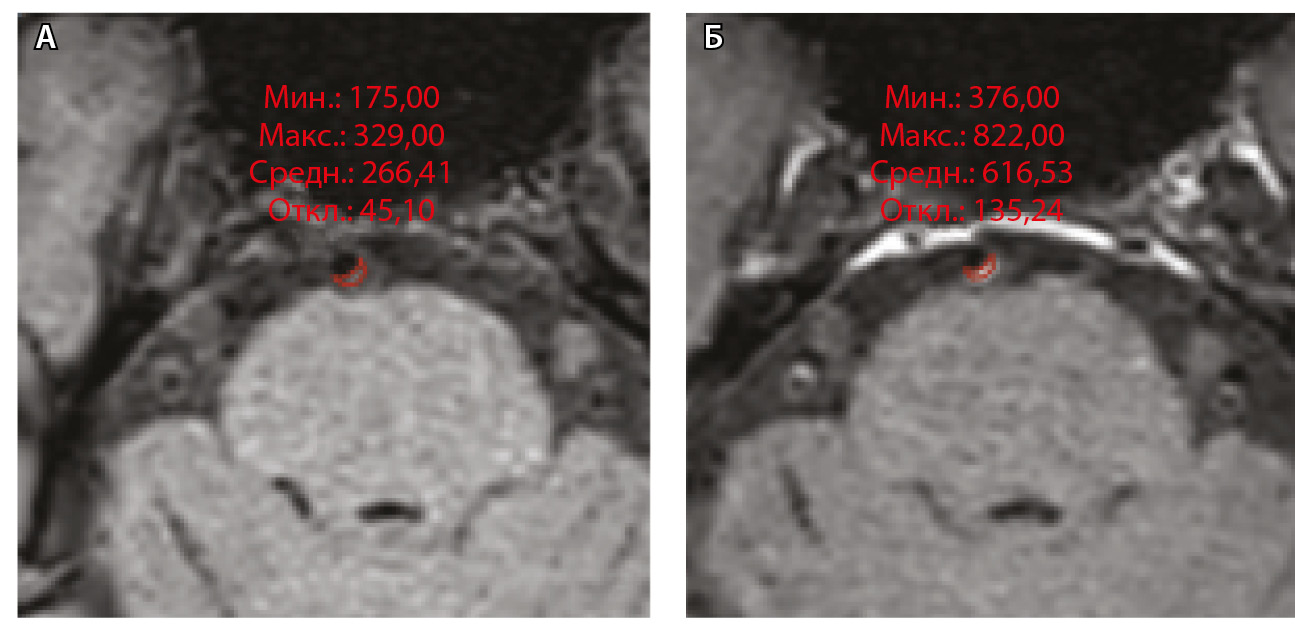

Для количественной оценки степени накопления контрастного вещества в области интереса (АСБ, неизмененная сосудистая стенка, воронка гипофиза) рассчитывали WEI по формуле:

,

где WEI (wall enhancement index) – индекс усиления контрастности стенки (сосудов), SIwallprecontrast – интенсивность сигнала (Signal Intensity, SI) сосудистой стенки (wall) в зоне интереса на преконтрастных (precontrast) изображениях, SIwallpostcontrast – интенсивность сосудистой стенки в зоне интереса на постконтрастных (postcontrast) изображениях; SIbrainprecontrast – интенсивность неизмененного белого вещества мозга (brain) на доконтрастных изображениях; SIbrainpostcontrast – интенсивность неизмененного белого вещества мозга на постконтрастных изображениях. Пример измерения интенсивности сигнала от АСБ для расчета WEI приведен на рисунке 1.

Рис. 1. Пример измерения интенсивности эхо-сигнала от атеросклеротической бляшки базилярной артерии для расчета индекса усиления контрастности стенки сосуда (WEI). В месте максимального стеноза артерии на одном срезе отмечали область интереса (ROI) и регистрировали среднее значение интенсивности сигнала от сосудистой стенки (SIwall). ROI были сопоставлены по размеру и местоположению в наборе данных T1-TSE-db-FS до (А) и после (Б) контрастного усиления; макс. – максимум, мин. – минимум, откл. – отклонение, средн. – среднее